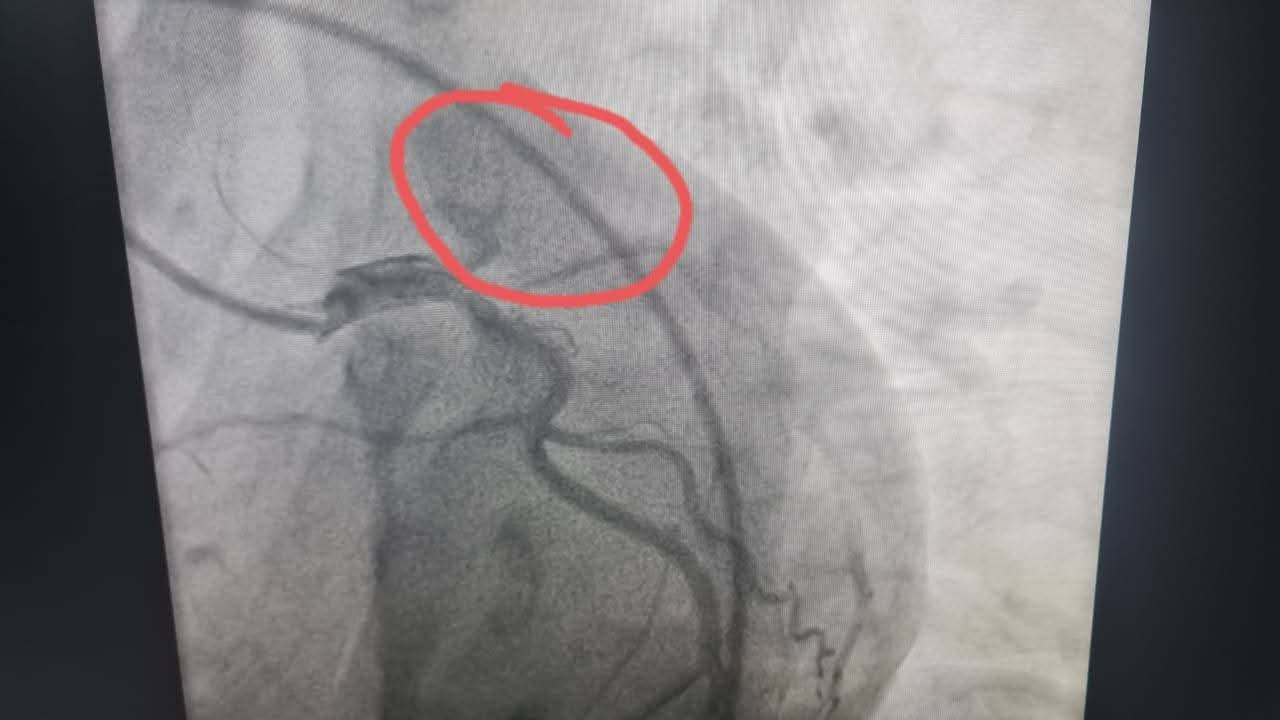

وأوضح الدكتور عمرو دويدار، وكيل وزارة الصحة بسوهاج، أن الشاب حضر إلى المستشفى في حالة حرجة ومتأخرة نسبيًا، وبعد إجراء رسم القلب والفحوصات اللازمة تبين وجود جلطة حادة بالشريان الأمامي وهي من الحالات النادرة جدًا في هذا العمر على المستوي العالمي.

وأضاف "دويدار" أنه فور الانتهاء من فحص المريض تم العرض على الفريق الطبي بوحدة قسطرة القلب، الذي قرر على الفور إجراء قسطرة قلبية عاجلة لاستكشاف الشرايين التاجية للقلب، حيث تبين أن الشريان الأمامي الرئيسي كان مسدودًا بالكامل، وتم فتح الشريان وتركيب دعامة بنجاح تام، واستقرت حالة المريض بعد العملية ويستكمل علاجه بالمستشفى.